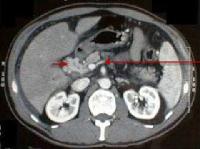

Foto 8: Tromboza de vena porta si transformare cavernoasa a venei porte la un pacient cu ciroza hepatica de etilogie alcoolica (sageata lunga indica vena splenica la jonctiunea cu vena mezenterica superioara, imediat inferior de tromboza, sageata scurta indica spre o forma serpigionoasa care indica transformarea cavernoasa a venei porte). |

Foto 9: Carcinom hepatocelular grefat pe o ciroya hepatica de etiologie alcoolica, complicat cu tromboza de vena porta (sageata scurta trombul cu o intrerupere brusca a traiectului portei, sageata lunga indica dezvoltarea circulatiei compensatorii). |